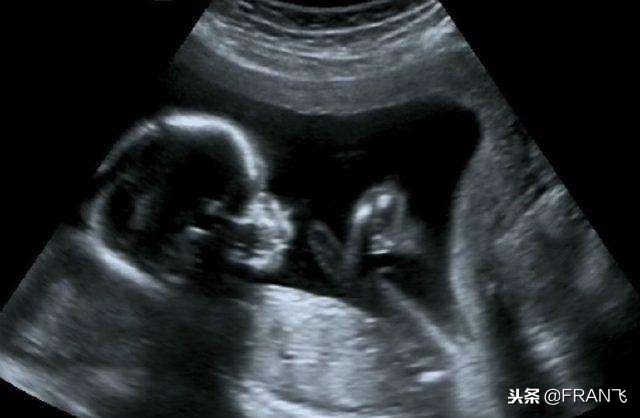

小李愁眉苦脸的拿着B超单回来,上面显示“怀孕6周”,医生看到后问:“好事啊,为什么不高兴”,小李说:“没有计划要孩子,而且已经吃过避孕药了,不知道这个孩子能不能要?”。医生说:“对于每个家庭来说,能够孕育一个小生命是多么伟大的事,但是比起怀孕的喜悦,能生出一个健康的宝宝更为重要,并不是所有情况下怀孕的宝宝都能要的,这5种情况下意外怀孕的宝宝不能要。”

虽然药物对胎儿有影响,但并非所有药物都对胎儿有影响。如果药物对胎儿有影响,胚胎多半会保不住。如果服用的并不是孕期禁用药,只要按时产检,在20周时照B超排畸,如果宝宝一切正常就好了。